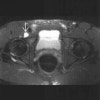

MRI : 장요 점액낭염(Iliopsoas bursitis, Iliopectineal bursitis)